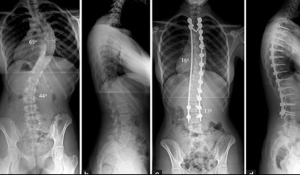

Chụp X-Quang giúp đánh giá hình thái xương, độ cong và sự sụt giảm khoảng cách giữa các đốt sống. Mặc dù không thể thấy rõ đĩa đệm, nhưng đây là bước đầu cần thiết để phát hiện thoát vị đĩa đệm gián tiếp qua hình ảnh cấu trúc xương.

Chụp X-Quang phát hiện thoát vị đĩa đệm có ưu điểm là chi phí thấp, thực hiện nhanh và an toàn. Tuy nhiên, phương pháp này thường được kết hợp cùng các kỹ thuật chuyên sâu khác để khẳng định chẩn đoán thoát vị đĩa đệm cột sống thắt lưng chính xác hơn.

Chụp X-Quang cột sống phát hiện thoát vị đĩa đệm

(Nguồn: Medlatec)